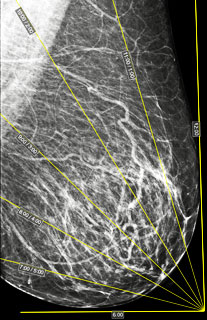

Correcting Markup on Oblique Projections:

Move the mouse cursor to the point located at the top of the corner (the front point of the nipple line)

Press and hold the left mouse button, move the mouse until the point aligns with the projection of the nipple, release the button

Repeat for the posterior point of the nipple line at the base of the breast

Move the mouse cursor to the top (12 o'clock) or bottom (6 o'clock) point

Press and hold the left mouse button, move the mouse until the boundaries of the extreme (12 and 6 o'clock) sectors coincide with the breast boundaries, release the button

If it's necessary to move the entire markup up or down; closer or farther from the image - similar actions, not on points, but on the sides of the angle